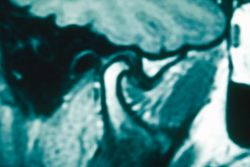

Non esiste una revisione sistematica in letteratura che affronti l'argomento menzionato in vivo, il che esalta l'importanza di questa sezione di Masticationpedia per capire quanto sia corretto o limitante fare diagnosi attraverso imaging (TC, Cone beam, MNR ecc.) in una manifestazione algico funzionale multifattoriale. (Figure 1,2 e 3)

L'interpretazione dell'imaging dell'ATM richiede una comprensione della normale anatomia dell'articolazione.

Come ben descritto dall'articolo di Seyed Mohammad Gharavi e coll.[8] la 'ATM è un'articolazione sinoviale tra la fossa glenoidea dell'osso temporale e il condilo mandibolare. La struttura anatomica centrale dell'ATM è il disco articolare o menisco. Il disco è una struttura fibrocartilaginea di forma ovale composta da bande articolari anteriori e posteriori e da un centro più sottile, chiamato zona intermedia. La zona intermedia conferisce al disco un aspetto biconcavo nella vista sagittale. La banda posteriore è generalmente più spessa della banda anteriore ed entrambe le bande sono più larghe nella dimensione trasversale che nella dimensione anteroposteriore. Il tessuto retrodiscale o zona bilaminare è un ricco tessuto neurovascolare che funge da attacco posteriore del disco, fondendo il disco con la capsula articolare e l'osso temporale. (Figura 5)